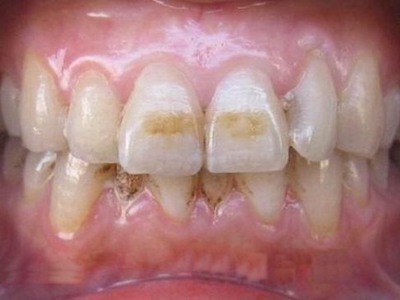

酸蚀症牙齿有黄斑轻微缺损图

酸蚀症症状较轻时,患者牙齿靠近牙根处有黄斑形成,有少量牙骨质缺损,出现较小的凹陷坑洼,该病多是长期接触外源性酸性物质或胃液反流导致。